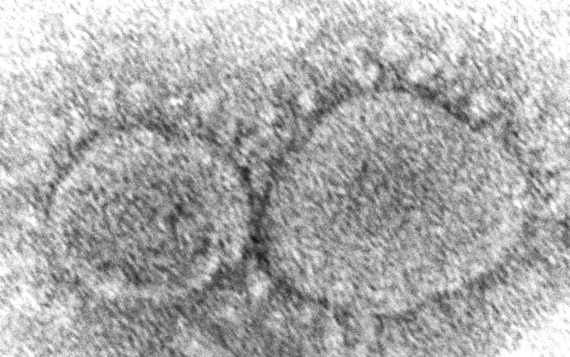

WHO '오미크론 변이' 공식 입장

"대규모 확산 가능성…매우 위험"이지예2021.11.29 23:34:48

'오미크론' 감염 확인, 시간과의 싸움

판독에 수일 걸려…속도 단축이 관건임재희2021.11.29 13:42:30

'오미크론 변이' 최소 14개국 확산

브라질도 의심사례…전 대륙 뚫리나김예진2021.11.29 11:29:31

파우치 "'오미크론', 면역 회피 가능성

이미 美 상륙했을수도…5차 유행 우려"김예진2021.11.29 07:34:49